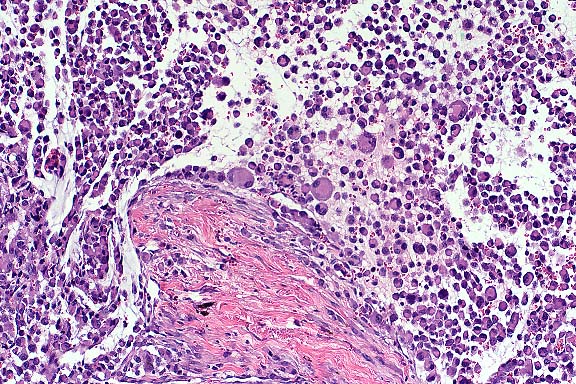

The normal anatomy of the filtration angle, iris, and ciliary body is effaced and expanded by an unencapsulated, infiltrative, cellular mass with lateral borders that extend through the width of the sclera. The mass consists of densely packed sheets and aggregates of pleomorphic round cells. Individual cells are large with abundant eosinophilic, often vacuolated cytoplasm, and generally distinct cytoplasmic borders. Nuclei are variable in shape and size with coarsely clumped or marginated chromatin and one to multiple nucleoli. Mitotic figures average 2-7 per high power field and often have bizarre morphology. Interspersed among these cells are multinucleated giant cells. There is phagocytosis of cellular debris and inflammatory cells by mononuclear and multinucleated cells. The cellular morphology of large pleomorphic mononuclear cells and multinucleated giant cells with abundant often vacuolated cytoplasm, as well as the observation that these cells are actively phagocytic suggests a histiocytic origin. Changes in the cornea and retina are considered secondary to glaucoma due to neoplastic obliteration of the filtration angle. An additional biopsy of a subcutaneous mass from this animal was composed of neoplastic cells of similar morphology to those infiltrating the eye.

Malignant histiocytosis is a familial disease of Bernese Mountain Dogs most predominantly affecting aging male dogs (mean age of onset 7 years). The disorder has a rapidly progressive clinical course and is characterized by proliferation of atypical histiocytic cells within multiple organ systems. Pulmonary, splenic, and hepatic involvement occurs with high frequency. The

eye and skin are rarely affected. In case studies, ultrastructural morphology and immunohistochemical demonstration of lysozyme and alpha-1-antitrypsin in the proliferating cells is consistent with a macrophage origin.

Case 4. Pleomorphic histiocytes & histiocytic giant cells are invading scleral collagen. (10x obj).

Conference Note: Conference participants agreed with the contributor's comments. Malignant melanoma and malignant histiocytosis were considered in the differential diagnosis. Malignant histiocytosis was favored due to a variety of factors, including evidence of phagocytosis by the neoplastic cells, the presence of many multinucleated cells, and the breed of the dog.